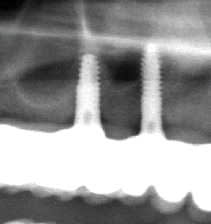

pour illustrer les propos pluton

cas d'un patient mâle caucasien 65 ans

sous plavix opéré de deux artères fémorales bouchées

interdiction d'interrompre le plavix

porte une PAT du haut depuis 30 ans

veut une prothèse fixe

radio de la zone délicate

implant placé avec Pilot version 2008 travaillant en lumière visible

forage 2mm flapless puis expansion